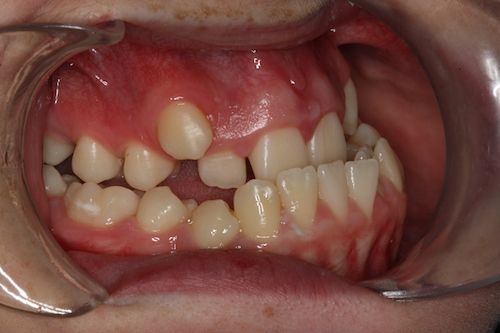

When the bones of the face and jaws are out of balance with each other, orthodontics alone will often not be able to position the teeth in order to create a functional bite. This imbalance between the jaws can result in a combination of problems. These may include:

- Difficulty eating due to teeth not meeting correctly

- Crowded, irregular teeth